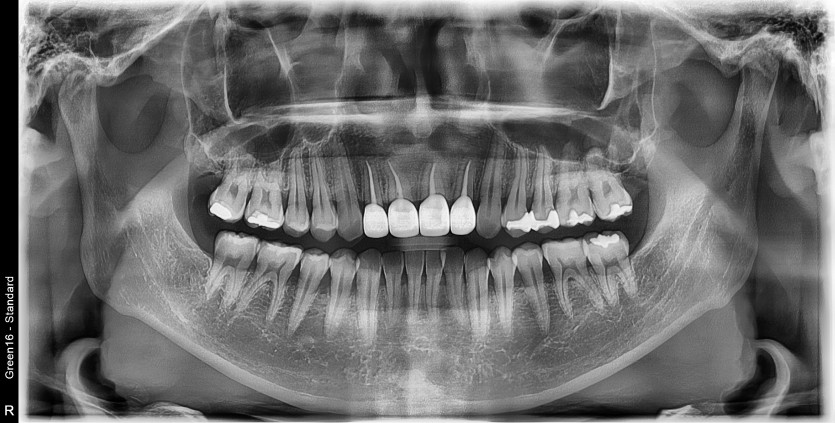

매복 과잉치와 낭종을 제거하고 치조골 이식을 진행하였습니다.